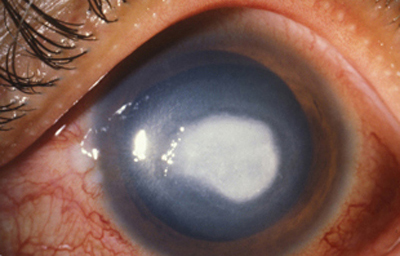

Superficie corneal irregular y grisácea, (Fig. 1, 2) con opácidades granulares en parche y formación de líneas epiteliales elevadas de aspecto granular (Fig. 3), que pueden arborizar dando imágenes de pseudodendritas. Opacidades superficiales satélites. (Figura 4) Inyección ciliar. Ulceración epitelial variante. (Figura 5).

Fig. 1 Síntomas de 15 días evolución